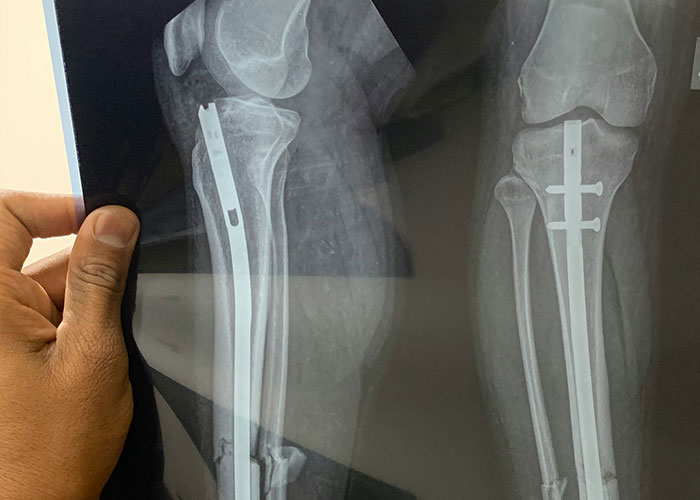

2) if you are getting any kind of orthopaedic surgery, there is probably some poor med student trying valiantly to hold your leg/arm at the perfect angle for the surgeon for an extended period of time and wishing they had lifted more weights because they also have to hold it in a way that maintains sterility and usually this means they are holding an adult humans’ entire dead weight of leg as far away from their own body as possible. I remember wishing I was swole.

4) Orthopaedics is basically human carpentry, with literal power tools. The blood gets everywhere. I would walk out of the OR with blood on my forehead that had managed to get over top of my clear visor.

During knee replacement they completely dislocate your knee, put the knee cap to the side, and start measuring and cutting. During tibia replacement part assists help push the tibia forward so you can apply components accurately.

During hip replacement the entire hip is dislocated, and if it’s old posterior approach, your femoral head is sticking out of the wound at like 45 degrees, roughly.

When you get a joint replacement revision, all bets are off. Freaking forget it. There is so much pulling, hammering, drilling. If it’s a hip you can lose so much blood you need a transfusion.